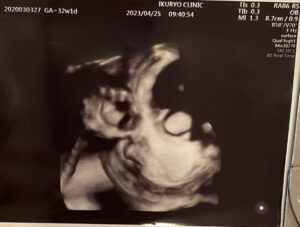

4Dのエコーの最中にお腹の中で赤ちゃんがすごく動いていて、映像が乱れていたのが怖かったです^^;

一応解説すると、向かって右側を向いていて、飛び出た丸いものが目です。笑

これを印刷してくれる先生のユーモア?は、なかなか気に入っています。